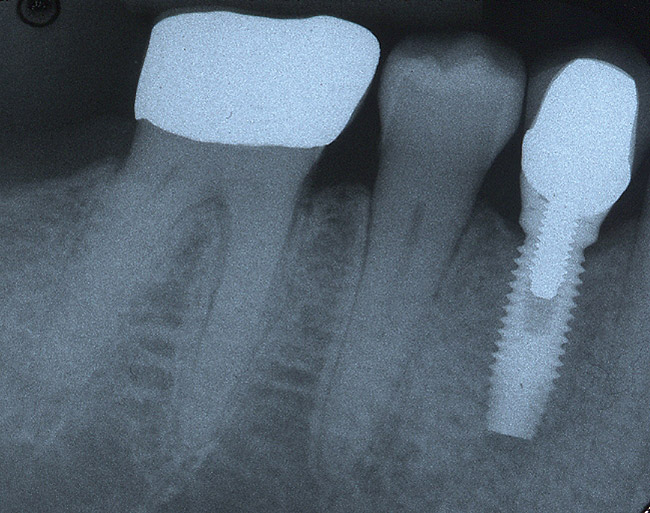

Implant placement was completed uneventfully, and after a healing period of about 3 months the implant was restored. The patient's tooth has been restored for about 5 years (Figure 2F).

Figure 2f: Implant placement was completed uneventfully, and after a healing period of about 3 months the implant was restored.

Figure 2f